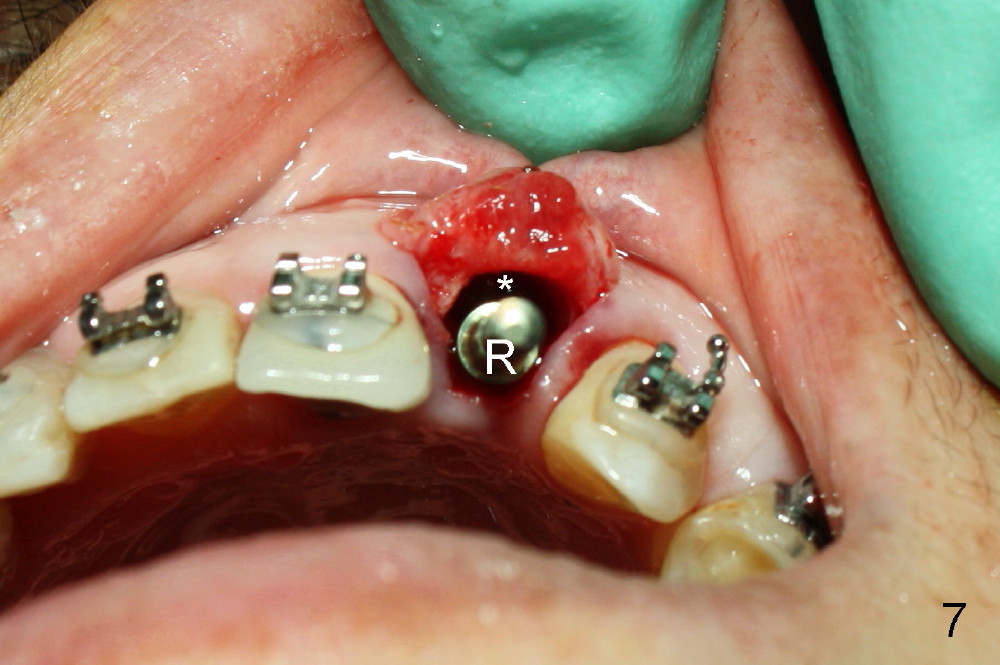

The 2.5 mm reamer is inserted as planned (following the contour of the alveolus (4)). Although the reamer (Fig.7 R) is palatal and there is a gap buccally (*), the handle of the reamer tilts buccally (Fig.8). A straight wall is created by using 2.5 mm reamer (Fig.9). A tapered implant is inserted (3.8x14 mm with apical diameter 2.4 mm, Fig.10). It is supposed to have high torque, but this implant is placed with a knob driver, probably due to osteoporosis. The dilemma is that the patient insists upon immediate provisional. If a tap driver were used, low torque would be found before implantation.